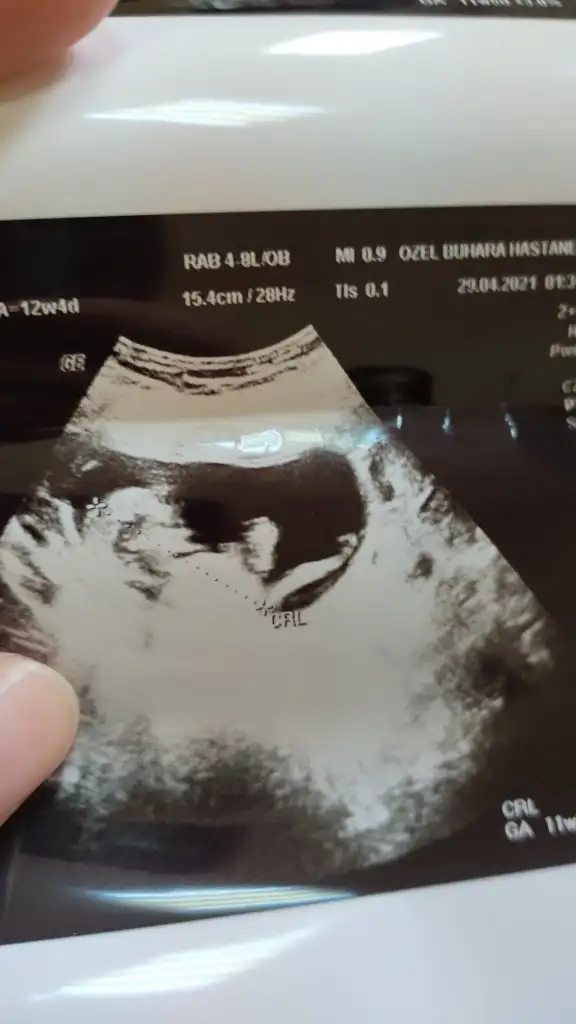

Emin olmadım kız gibi sanki tekrar USG paylasinIkra meyra merhabalar sanırım nub belli değil ama şansımı denemek istedim 11+2 yiz bugün tahmininiz nedir

Nedense hiç düzgün çekilmemiş bir de bu var bu gündenEmin olmadım kız gibi sanki tekrar USG paylasin